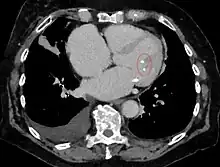

Coupe scanographique axiale montrant des calcifications aux extrémités des muscles papillaires de la valve mitrale du cœur (cercle rouge).